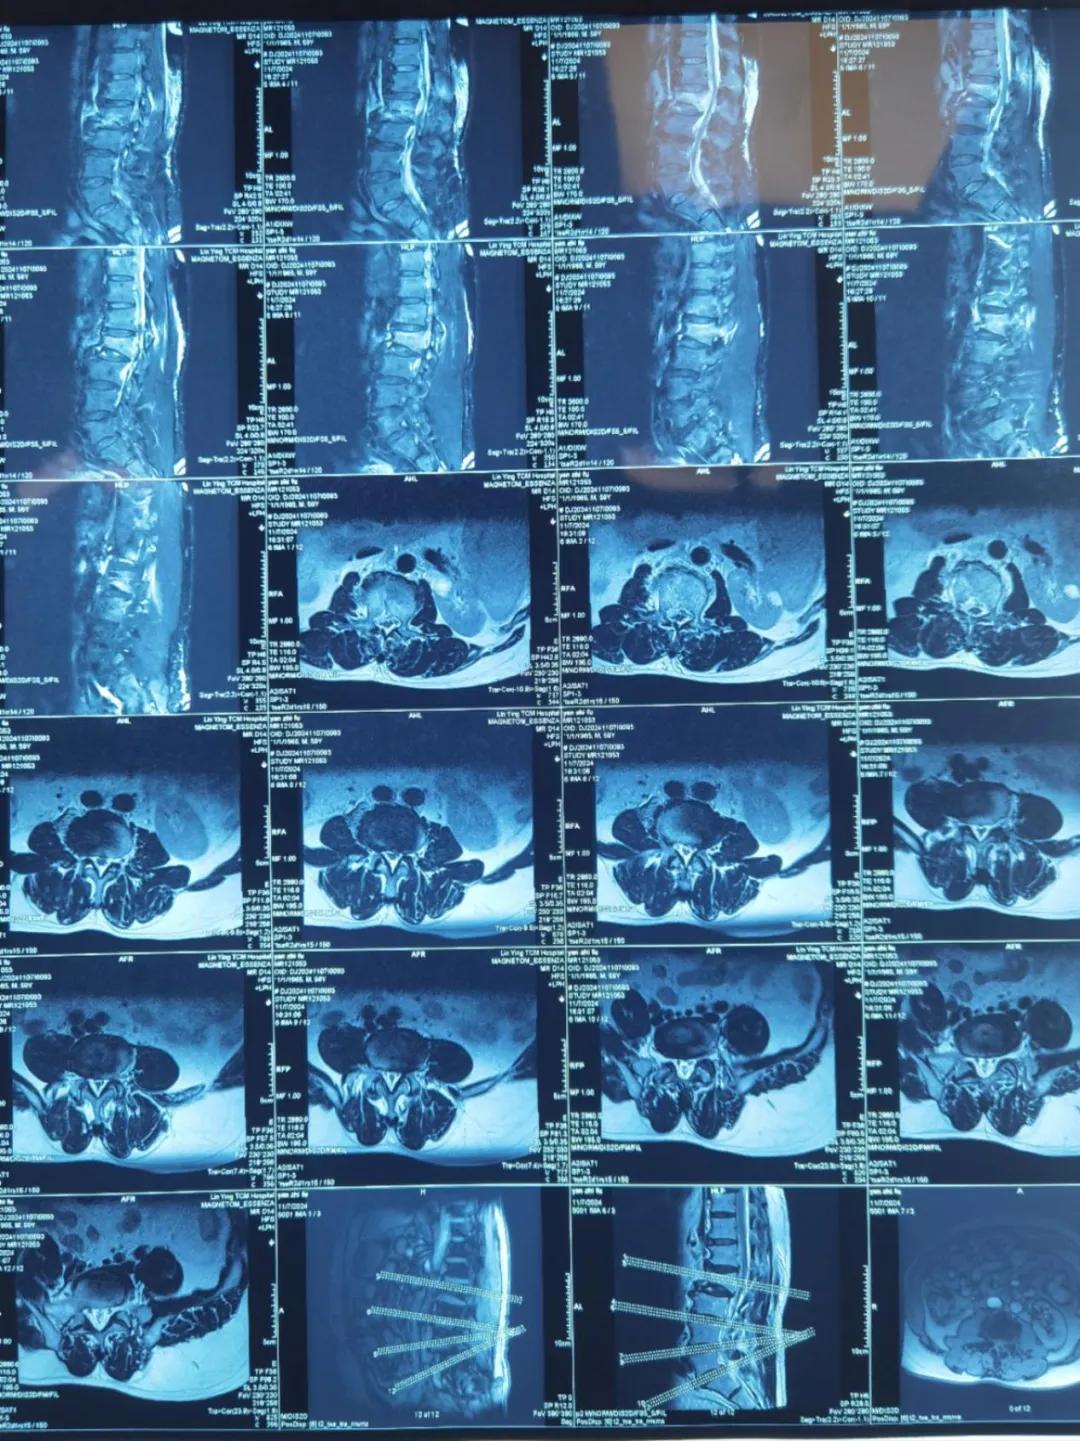

“醫(yī)生,這是之前的檢查結(jié)果,還需要再做檢查嗎?”閆大叔從外院轉(zhuǎn)來(lái)被推進(jìn)智能微創(chuàng)骨科。幾天前,他在老家的中醫(yī)院進(jìn)行了抽血檢驗(yàn)和磁共振檢查,因?yàn)檠蹏?yán)重、行動(dòng)不便檢查過(guò)程也十分不易。

智能微創(chuàng)骨科副主任李鵬認(rèn)真檢查了閆大叔帶來(lái)的片子,還有電腦系統(tǒng)上彈出來(lái)的檢驗(yàn)結(jié)果。外院的核磁和X線可以清楚的看到情況已經(jīng)比較嚴(yán)重,需要盡快手術(shù)。沒(méi)有二次檢查,不僅節(jié)省患者就醫(yī)費(fèi)用,還使就醫(yī)更高效、便捷直接入院接受治療。閆大叔懸著的心放了下來(lái),其他醫(yī)院的片子能直接用,檢查在家附近的醫(yī)院做,手術(shù)在漯河市骨科醫(yī)院做,便捷的結(jié)果'互認(rèn)'讓他直夸“真方便!咱老百姓更省心、更放心了!”